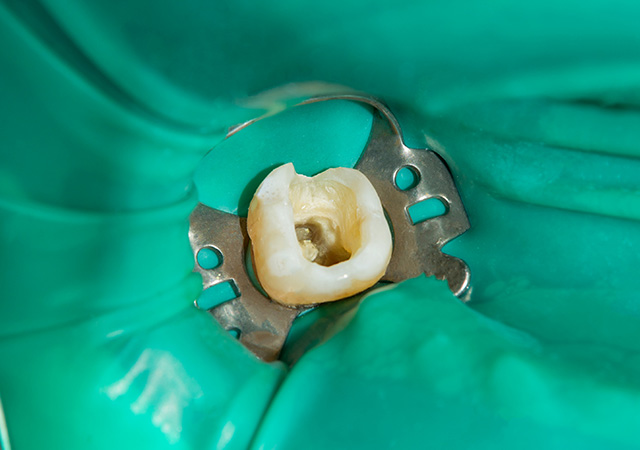

ラバーダム防湿は、根の治療(根管治療)を成功させるためには重要です。ラバーダム防湿とは、治療する歯以外を薄いゴム製シートで覆い被せ、口腔内の唾液や細菌の感染を防止する道具です。ラバーダムを使用することで、唾液中に含まれる様々な口腔内細菌が根管に侵入するのを防ぎ、無菌的な処置を行うことが可能になります。ラバーダム防湿を行わないで行う根の治療(根管治療)は細菌感染の可能性が高まりますので、当院ではラバーダムの使用が難しい場合を除いては、使用しています。

根管治療を行うのは、菌が神経まで達した深いむし歯のため、上部の歯を削り、汚染された根管が見えやすい状態にします。